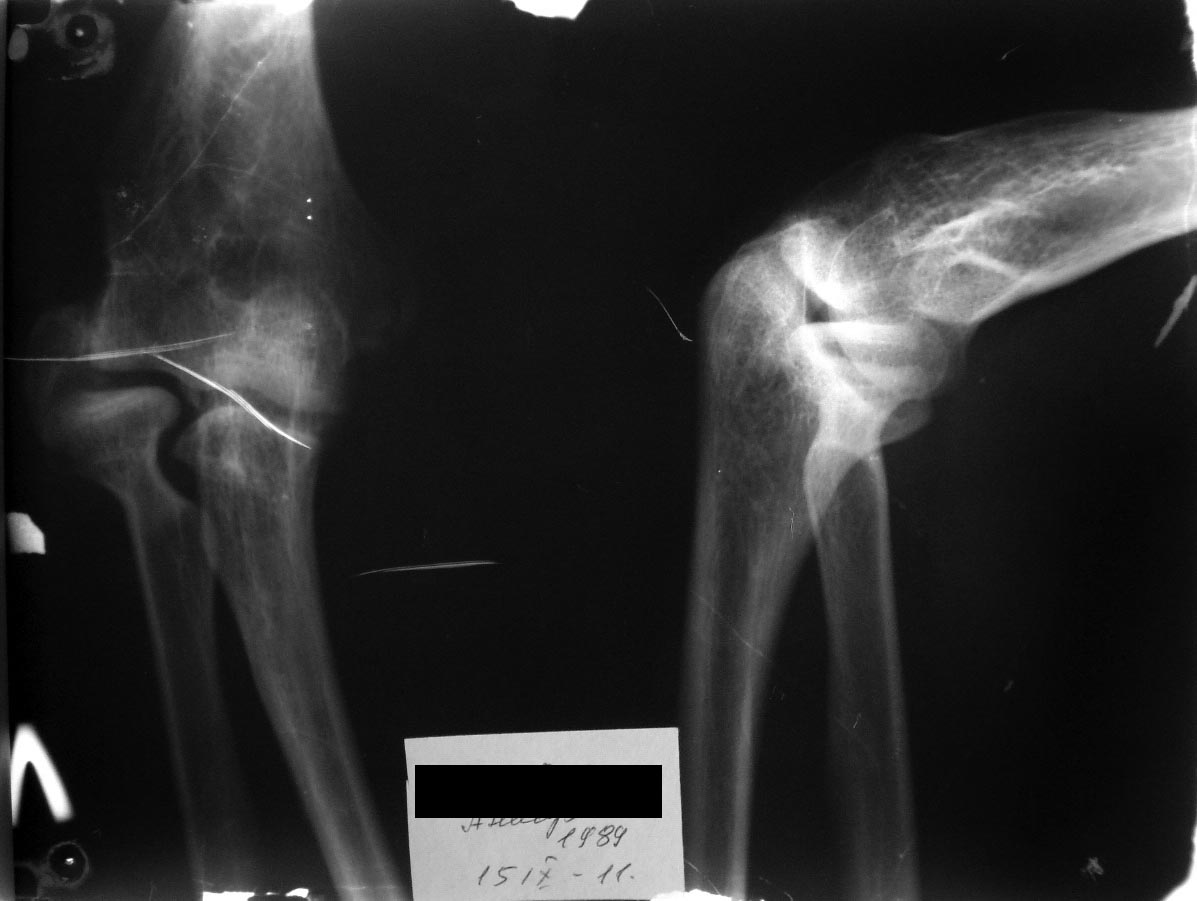

Молодой человек, 21 год. Перелом латерального надмыщелка 7 лет назад.

Лечили консервативно, гипсовая иммобилизация без должного контроля.

В настоящий момент беспокоит ограничение амплитуды движений в локтевом

суставе, деформация локтевого сустава (за счет смещенного фрагмента).

Есть ли смысл браться за скальпель и долото? Беспокоит вопрос насколько

улучшится функция локтевого сустава? Думаю отделить фрагмент и поставить

его на место, фиксировав двумя винтами ( 1 в блок, 2ой в латеральную

колонну). Также беспокоит вопрос латеральной боковой связки, даст ли она

поставить все на место... Буду рад услышать мнение коллег по этому поводу...